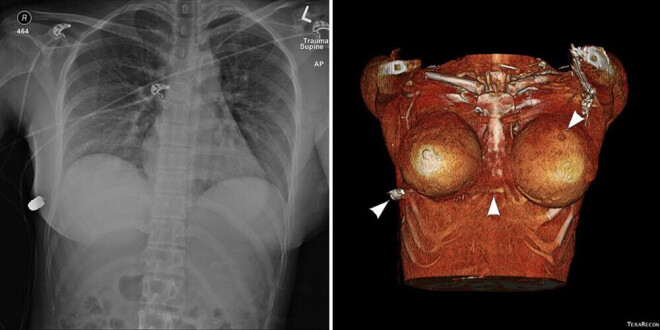

Свидетели вызвали скорую, пострадавшую доставили в ближайший травмпункт в стабильном состоянии. Доктора осмотрели ее и обнаружили лишь небольшое отверстие от пули в верхней части левой груди. Под кожей правой груди пациентки врачи нащупали нечто, напоминающее пулю. Канадке сделали рентгеновский снимок, который подтвердил подозрения врачей. Как выяснилось, пуля сломала одно ребро пациентки и застряла в правой боковой стенке ее грудной клетки.

Компьютерная томография выявила небольшой ушиб легкого, однако серьезных повреждений органов грудной клетки удалось избежать.

Врачи внимательно изучили компьютерную томографию пациентки и сделали вывод, что, если бы у нее не было имплантов, то пуля должна была пройти прямо через ее грудную стенку и, возможно, поразить ее сердце.

«Исходя из клинической траектории проникновения пули и радиологической оценки, единственным источником отклонения пули является левый имплантат молочной железы. Этот имплантат перекрывает сердце и внутригрудную полость и поэтому, вероятно, спас жизнь женщины», — написали авторы исследования.